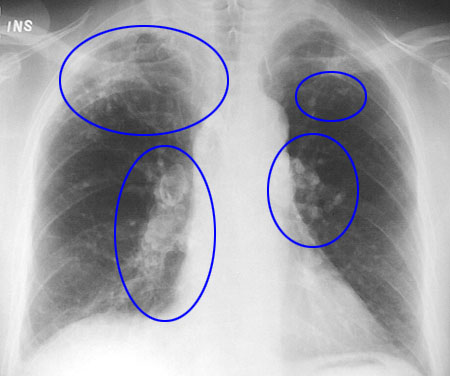

Respiratory effects

In some eruptions, ash particles can be so fine that they are

breathed deep into the lungs. With high exposure, even healthy

individuals will experience chest discomfort with increased

coughing and irritation.

In rare circumstances, long-term exposure to fine volcanic ash may lead to serious lung diseases. For these diseases to occur, the

ash must be very fine, contain crystalline silica (for the disease silicosis to occur) and the people must be exposed to the ash in

high concentrations over many years. Exposure to crystalline silica in volcanic ash is typically of short duration (days to weeks),

and studies suggest that the recommended exposure limits (similar in most countries) can be exceeded for short periods of

time for the general population.

People suffering from asthma or other lung problems such as bronchitis and emphysema, and severe heart problems are most at risk.

Why are people with chronic lung problems at special risk?

The fine ash particles irritate the airways and cause them to

contract, making breathing more difficult in people who already have

lung problems. The fine dust also causes the lining of the airways to

produce more secretions which can cause people to cough and breathe

more heavily. Asthma sufferers, especially children who may be

heavily exposed to the ash when they play, may suffer bouts of

coughing, tightness of the chest and wheezing. Some people who have never knowingly had asthma before, may experience asthma symptoms following an ash fall, especially if they go outdoors in the ash and over-exert themselves.